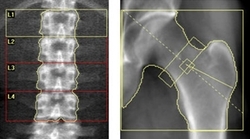

骨密度検査

当院では、骨密度検査の中で最も精度が高いとされているDXA法を用いた装置で検査を行っています。腰椎と股関節の骨密度を測定することでより正確な骨粗鬆症の診断を行います。骨密度は健康寿命を左右するとも言われていますので、特に50歳以上の女性の方には骨密度検査をおすすめいたします。

ホロジック:Horizon W |